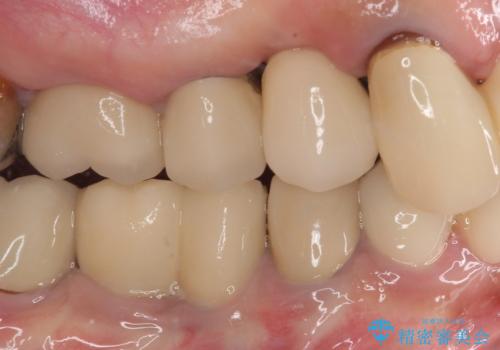

膿の出口が認められた頬側の歯槽骨は欠損が大きかったものの、インプラント埋入には十分な骨があり、無事に短期間で治療を終えることができました。